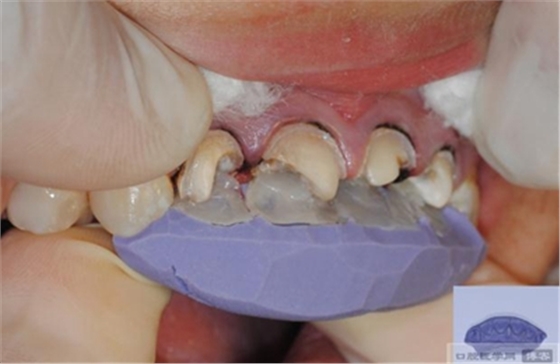

【纖維樁制作】

修整纖維樁長度

取出纖維樁,按所需長度裁截纖維樁 在有水條件下 用切割砂片或車針截取纖維樁,切勿使用鉗子,剪刀或鑷子以免破壞樁的結(jié)構(gòu)

將樹脂粘接劑均勻涂抹在根管、牙體的粘接面以及纖維樁表面,涂抹兩遍

粘接

將調(diào)好的樹脂水門汀用口內(nèi)注射頭送入根管

將纖維樁表面涂滿調(diào)好的樹脂水門汀,安放在根管內(nèi)就位,保持壓力10秒